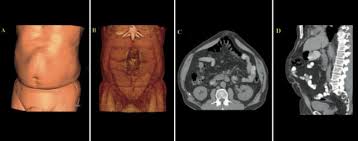

La diastasi si manifesta come una depressione a livello della linea mediana dell'addome che diventa una tumefazione all'aumentare della pressione addominale (facendo addominali, con il ponzamento). Solitamente può associarsi anche un'ernia ombelicale.

La diastasi può essere localizzata nel tratto sopra o sotto l'ombelico o coinvolgere tutto l'addome. Spesso alla diastasi si associa anche un addome pendulo e la presenza di smagliature. In questi casi alla riparazione della diastasi può associarsi la plastica dell'addome (Addominoplastica).